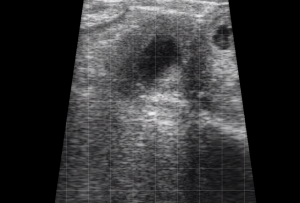

SIMON Ultrasound Database

This ultrasound database is a free resource for students and doctors!

Our collection includes videos of dogs, cats, horses, cows, humans, and many other species!